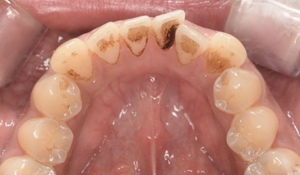

CASE 10

Before①

After①

Before②

After②

基本情報

| 年齢・性別 | 38歳・男性 |

|---|---|

| 主訴 | 下顎 歯石除去したい |

| 治療内容 | スケーリング |

| 治療期間 | 30分 |

| 治療費 | 約1,500円(保険診療) |

| リスク・副作用 | 知覚過敏、歯肉退縮 |

| 治療方針 | 歯肉縁上歯石を除去してから歯肉縁下歯石を除去します。ご自身でのプラークコントロールができるようになったら定期検診に移行します。 |

| 担当者所見 | 半年ぶりの歯科医院の受診。歯石が付きやすいためセルフケアの重要性をお伝えして、定期的にクリーニングを行います。出血率が高く炎症が強いため、今後はセルフケアを強化して歯周病治療を行います。 |